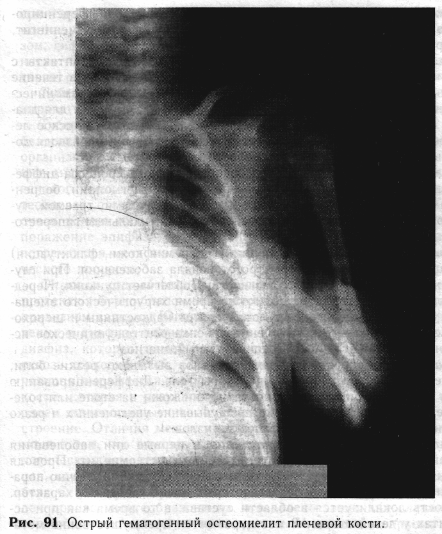

Контрольные рентгенограммы производят на 10-12-й день заболевания. К этому времени появляется первый рентгенологический признак острого остеомиелита длинных трубчатых костей: рядом с тенью коркового слоя диафиза или метафнза появляется периостит в виде тонкой линейной пластинки, идущей вдоль кости (рис. 91). Протяженность периостита зависит от степени отслойки надкостницы экссудатом